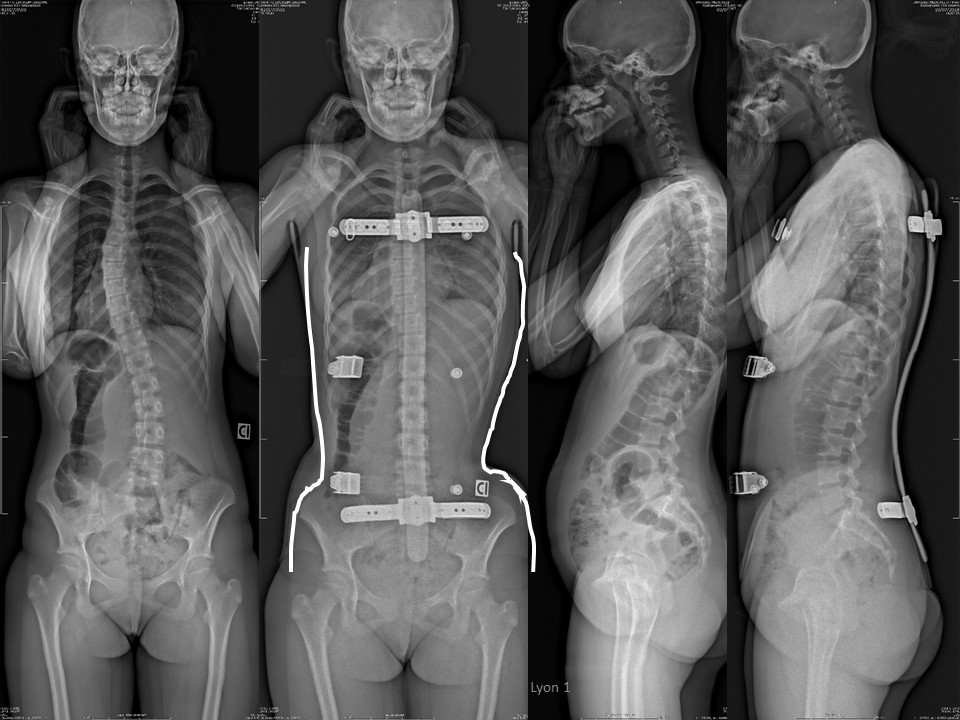

Confirmation is provided by studying the 3 successive scans produced for ARTbrace. During the moulding n ° 1 carried out in extension, the two girdles remain balanced without rotation. |

|

During scan No. 2 at the lumbar level, a first detorsion is noted between the pelvic girdle and the shoulder girdle. |

This detorsion between the two girdles is accentuated during scan No. 3 performed at the thoracic level. |

Here is the result of this case n° 90, with initially thoracic scoliosis of 39° and rib hump of 17° ATR. Excellent in-brace correction with total reduction of the curvature. The sagittal plane is also improved, |

Under EOS 3D, detorsion is excellent with centring of the vertebrae on the midline |

Here is the Clinical picture in brace. |